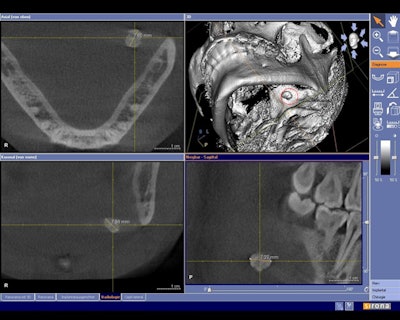

![]() Cone-beam CT dataset showing a slightly overaverage size salivary calculus of 7-8 mm in the left submandibular gland area in the axial (upper left), coronal (lower left), and sagittal (lower right) view. Maximal diameters were measures using the visualization software tools. In the 3D reconstruction (upper right), the reformatted 3D salivary calculus is visualized and marked with a red circle. All images courtesy of Timo Dreiseidler, M.D., D.M.D., University of Cologne. |